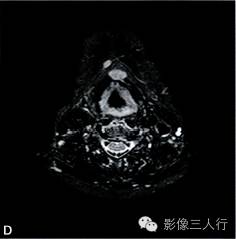

A~B. T1WI横断位;C~D. T2WI压脂横断位; E~F. T1WI压脂增强横断位;G. HE×100

卵圆形结节影位于舌骨中线,T1WI呈低信号,T2WI压脂序列呈稍高信号,信号均匀。增强后明显均匀强化,约1.3cm×0.8cm×1.6cm,其右前方下颌间隙内亦见一小结节,约0.7cm×0.4cm×0.5cm,信号特点与舌骨中线结节大致相同。颈部软组织结构清楚,未见异常信号影,气管居中,无受压或移位。颈部MRI平扫两侧见正常甲状腺组织,信号欠均匀(图A~F)。